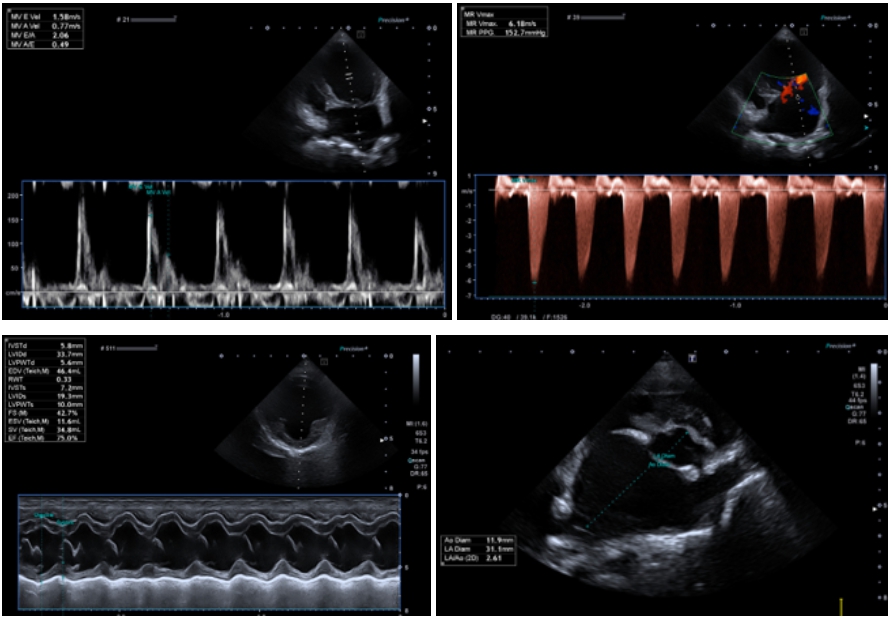

심장초음파

이첨판 폐쇄부전증(MMVD) – ACVIM Stage C, 심인성 폐수종(CPE)

심장초음파 검사 결과, MV(이첨판)의 변성과 함께 중등도 이탈(moderate prolapse) 이 확인되었으며, 심한 이첨판 역류(Severe MR) 가 동반되어 있었습니다.(역류 속도 Vmax 6.18 m/s)

심장 내 압력 상승으로 인해 좌심방 용적이 비정상적으로 증가된 상태였으며 (LA/Ao 2.7, LA diameter 32.9 mm), 좌심실 이완기말 용적 증가도 확인되었습니다. (LVIDDN 2.3)

또한 심장의 부담이 커지면서 좌심방 압력 상승 소견(E peak 1.58 m/s)이 관찰되었습니다. Mild TR(삼첨판 역류)은 확인되었으나, 우심실의 크기와 기능은 비교적 양호한 상태였으며 폐고혈압(PH) 가능성은 낮게 평가되었습니다.

결론적으로, 아이는 심장 기능 저하로 인한 중증 이첨판 역류와 그에 따른 심한 심장 비대 상태로, 심부전 단계에 도달한 MMVD C 단계로 진단되었습니다. ▼